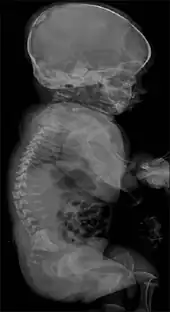

It is a lethal rhizomelic (malformations which result in short, underdeveloped limbs) form of dwarfism,[1] exhibiting both skeletal dysplasia (malformations of bone) and fibroblastic dysplasia (abnormal development of fibroblasts, specialized cells that make up fibrous connective tissue, which plays a role in the formation of cellular structure and promotes healing of damaged tissues).[4][5][6] Death caused by complications of fibrochondrogenesis occurs in infancy.[6]

Other prominent features include dwarfism,[1] shortened ribs that have a concave appearance,[6] micrognathism (severely underdeveloped jaw),[7] macrocephaly (enlarged head),[8] thoracic hypoplasia (underdeveloped chest),[8] enlarged stomach,[8] platyspondyly (flattened spine),[6] and the somewhat uncommon deformity of bifid tongue (in which the tongue appears split, resembling that of a reptile).[7]